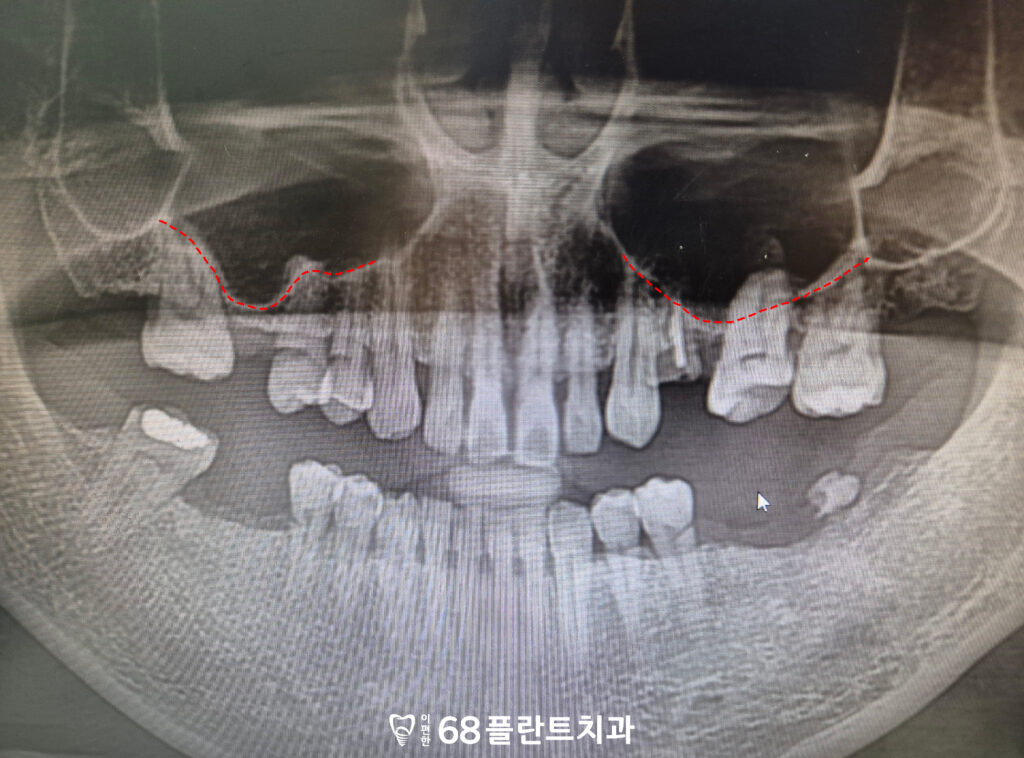

파노라마 사진을 통해 진단해 보니,

왼쪽 위 치아는 머리 부분이

완전히 부러져 저작 기능을

전혀 할 수 없는 상태였습니다.

다른 부위도 치아가

상실되어 있었습니다.

이런 경우 방치하면 교합이 무너지고,

치아 배열에도 불균형이

생길 수 있습니다.

임플란트를 안정적으로 식립하려면

잇몸뼈의 두께와 높이가

충분히 확보되어야 합니다.

하지만 환자분의 경우

상악동과 치조골 사이의

거리가 매우 가까워

임플란트를 지탱할 만한

뼈의 높이가 부족했습니다.